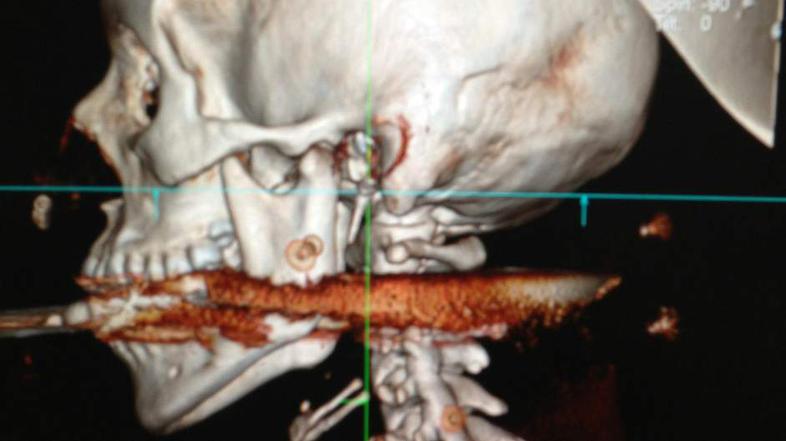

Mož s harpuno ustrelil ženo v usta

Neko Brazilko je mož med čiščenjem harpune ponesreči ustrelil in jo zadel v usta. Harpuna je prebila njeno hrbtenico, a je preživela, čeprav jo je od smrti ločil le en centimeter.

Elisangela Borborema Rosa je imela srečo v nesreči. Ko je mož v ponedeljek čistil harpuno, se je ta ponesreči sprožila in jo zadela v usta ter ji prebila hrbtenico. Osemindvajsetletnico so nemudoma odpeljali v bolnišnico, kjer so ji nudli nujno zdravniško pomoč. Nevrokirurg Allan da Costa je pojasnil, da je Elisangela izven smrtne nevarnosti in da bo popolnoma okrevala. "Če bi jo harpuna zadela en centimeter v drugo stran, bi postala tetraplegik, če pa bi šla za en centimeter v drugo smer, bi bila mrtva."